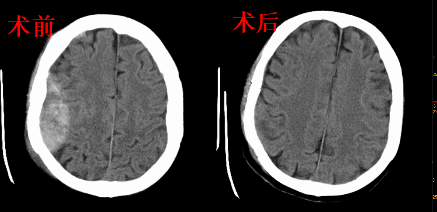

脑出血:

4.内镜下基底节区血肿清除+还骨瓣